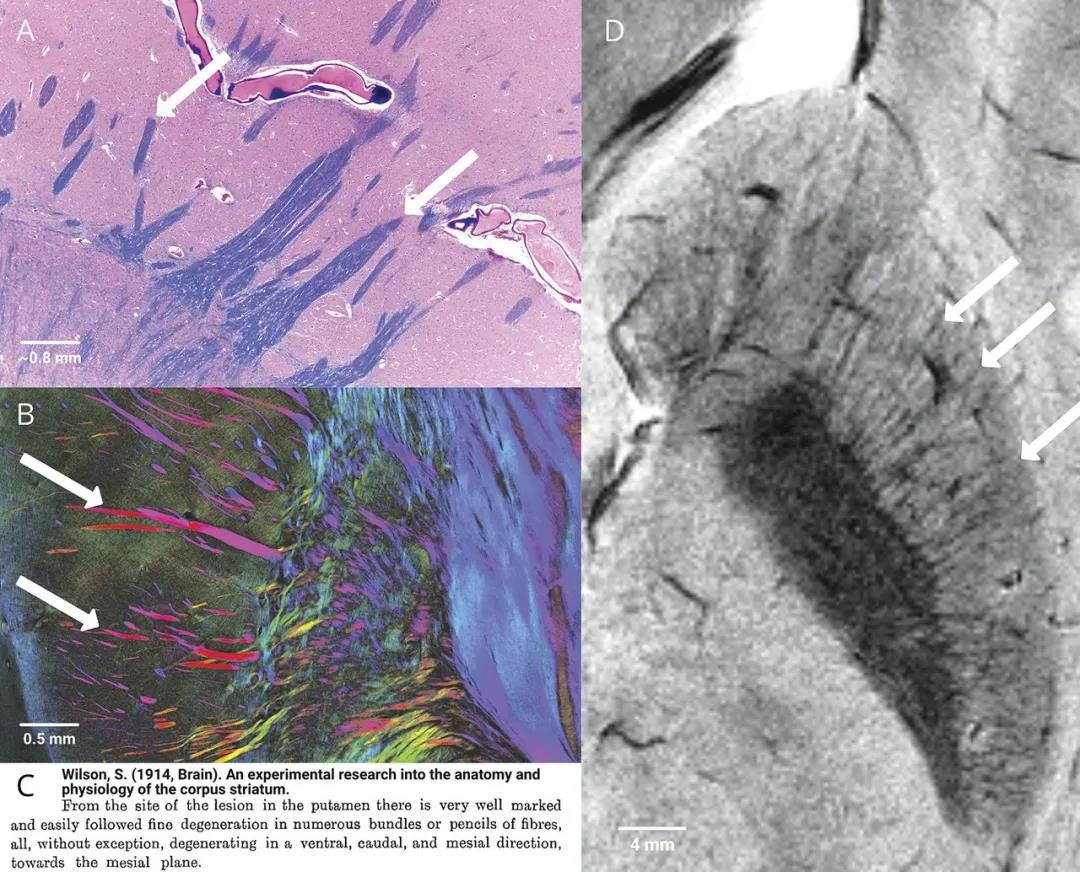

纹状体之所以称为纹状体,是因为来自大脑皮层的投射形成纤维束(很多个神经细胞的“手”绑在一起成束),在解剖上就形成了条纹。该条纹也称为Wilson’s pencils,因神经病学家S.A. Kinnier Wilson(1878-1937)将其描述为“像铅笔一样的”神经纤维束(图7)。

图7. 纹状体的条纹(箭头所示),又称Wilson’s pencils或the pencil fibers of Wilson[17]。(点击看大图)